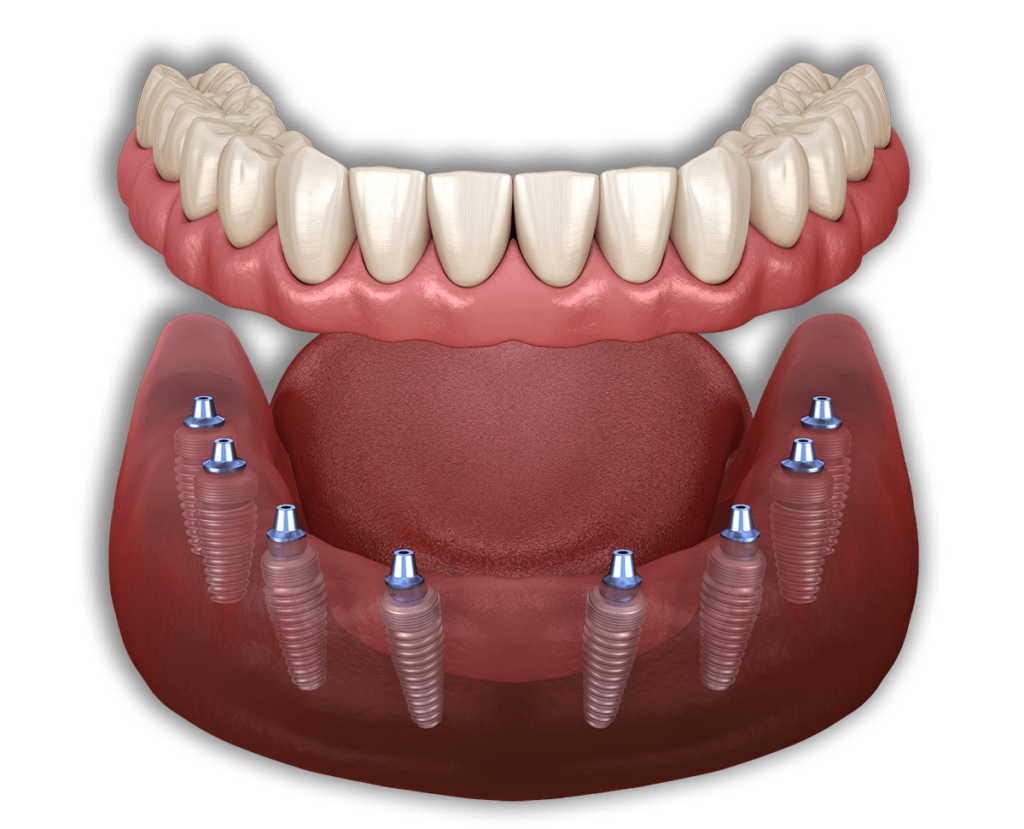

All on 8

Tutti gli 8 impianti dentali vengono utilizzati in pazienti che richiedono una maggiore sicurezza dei loro impianti ad arcata completa. Ciò potrebbe essere dovuto alla scarsa densità della mascella, alla forma irregolare della bocca o a qualsiasi altro problema riscontrato dal dentista.